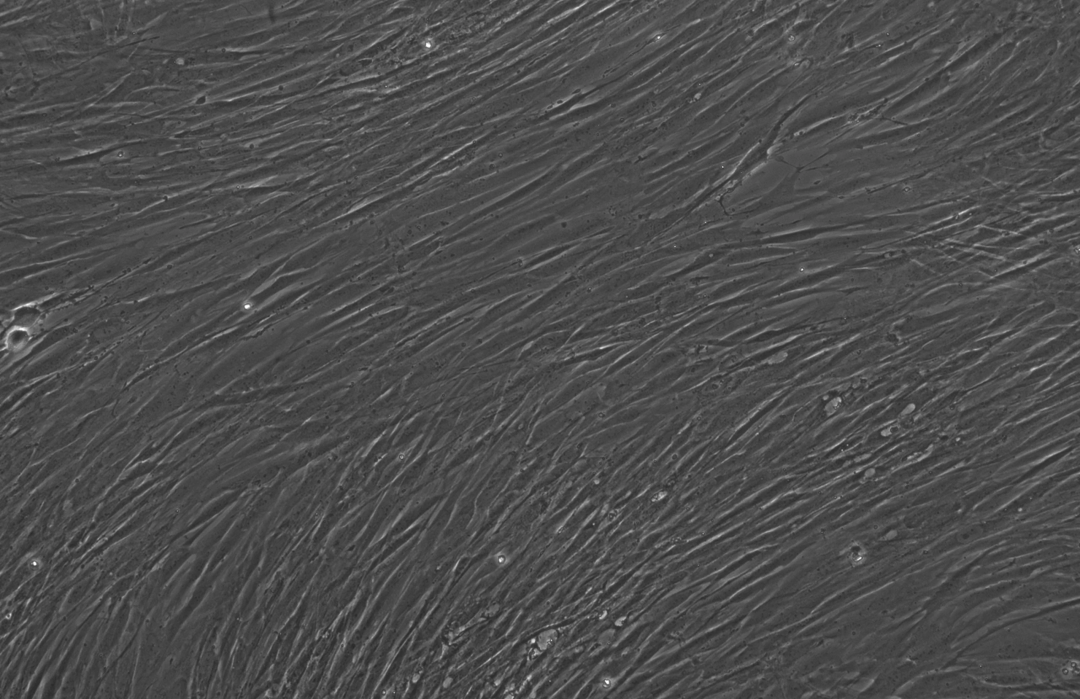

下面这三张图展示的是,OpenAI设计的蛋白质能更高效地诱导干细胞重编程:

使用RetroSOX与RetroKLF变体(结合OCT4, MYC)重编程10天后,出现了大量具有紧凑、圆形形态的集落,这是细胞迈向iPSC状态的典型特征